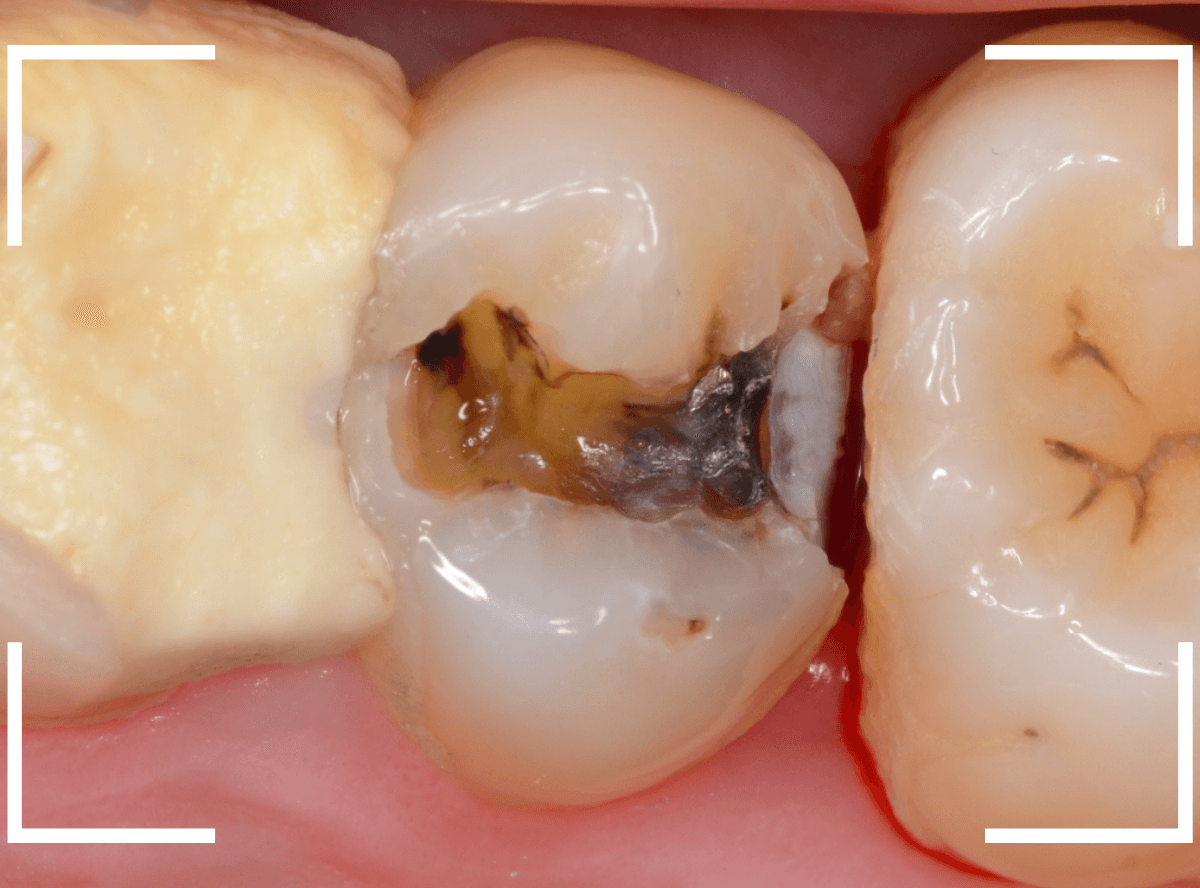

Case.22 痛みはないけど、歯のすきまから大きな虫歯

上の小臼歯の間が虫歯になっていた患者さんです。

症状はありませんし、見た目からも虫歯があるかはわかりませんでした。

レントゲン写真で確認します。

赤い線が虫歯、青い線が歯の神経です。

歯のすきまから両側に虫歯が大きく広がっているのが確認できます。

治療を開始します。

少し削ると、中からすぐに虫歯が出てきました。

ある程度、虫歯を除去したところで、う蝕検知液で確認します。

赤く染まっている部分が虫歯です。

まだまだ虫歯が中で残っている状況で、かなり深い虫歯なのが確認できます。

全ての虫歯を除去しました。

レントゲン写真からある程度確認出来ましたが、歯の神経スレスレまで虫歯が進行していました。

ここまで虫歯が進行していても、全く症状を感じない事も多いです。

そして、ある時急に痛みを感じるのです。

虫歯は急に進行しません。

治療後の定期検診で確実に食い止めましょう。